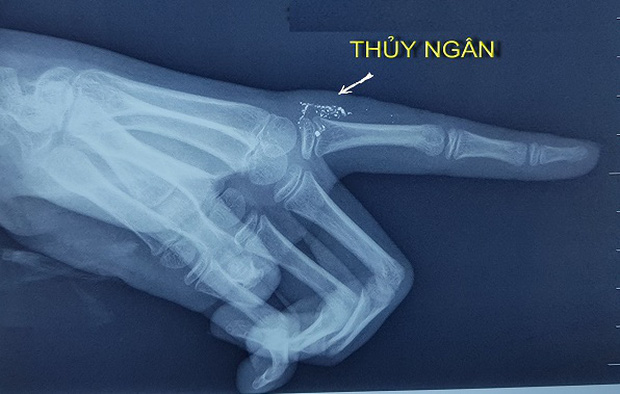

Hình ảnh những hạt thủy ngân trong tay qua hình ảnh phim X-quang (Ảnh: BVCC)

Khi vào viện, vết thương của bé đã bị nhiễm trùng và áp xe. Các bác sĩ chụp X-quang ngón tay của cháu thấy có nhiều hạt thủy ngân ở bên trong phần mềm sát khớp bàn ngón trỏ tay trái.

Bác sĩ cho biết dự kiến vị trí phẫu thuật nhỏ nhưng cuộc mổ rất đặc biệt do cần phải lấy hết các hạt thủy ngân ra ngoài an toàn. Các bác sĩ đã chụp cắt lớp, siêu âm để đánh giá kỹ số lượng hạt thủy ngân và vị trí thủy ngân chính xác ở ngón tay để chuẩn bị cho cuộc mổ loại bỏ các hạt thủy ngân.